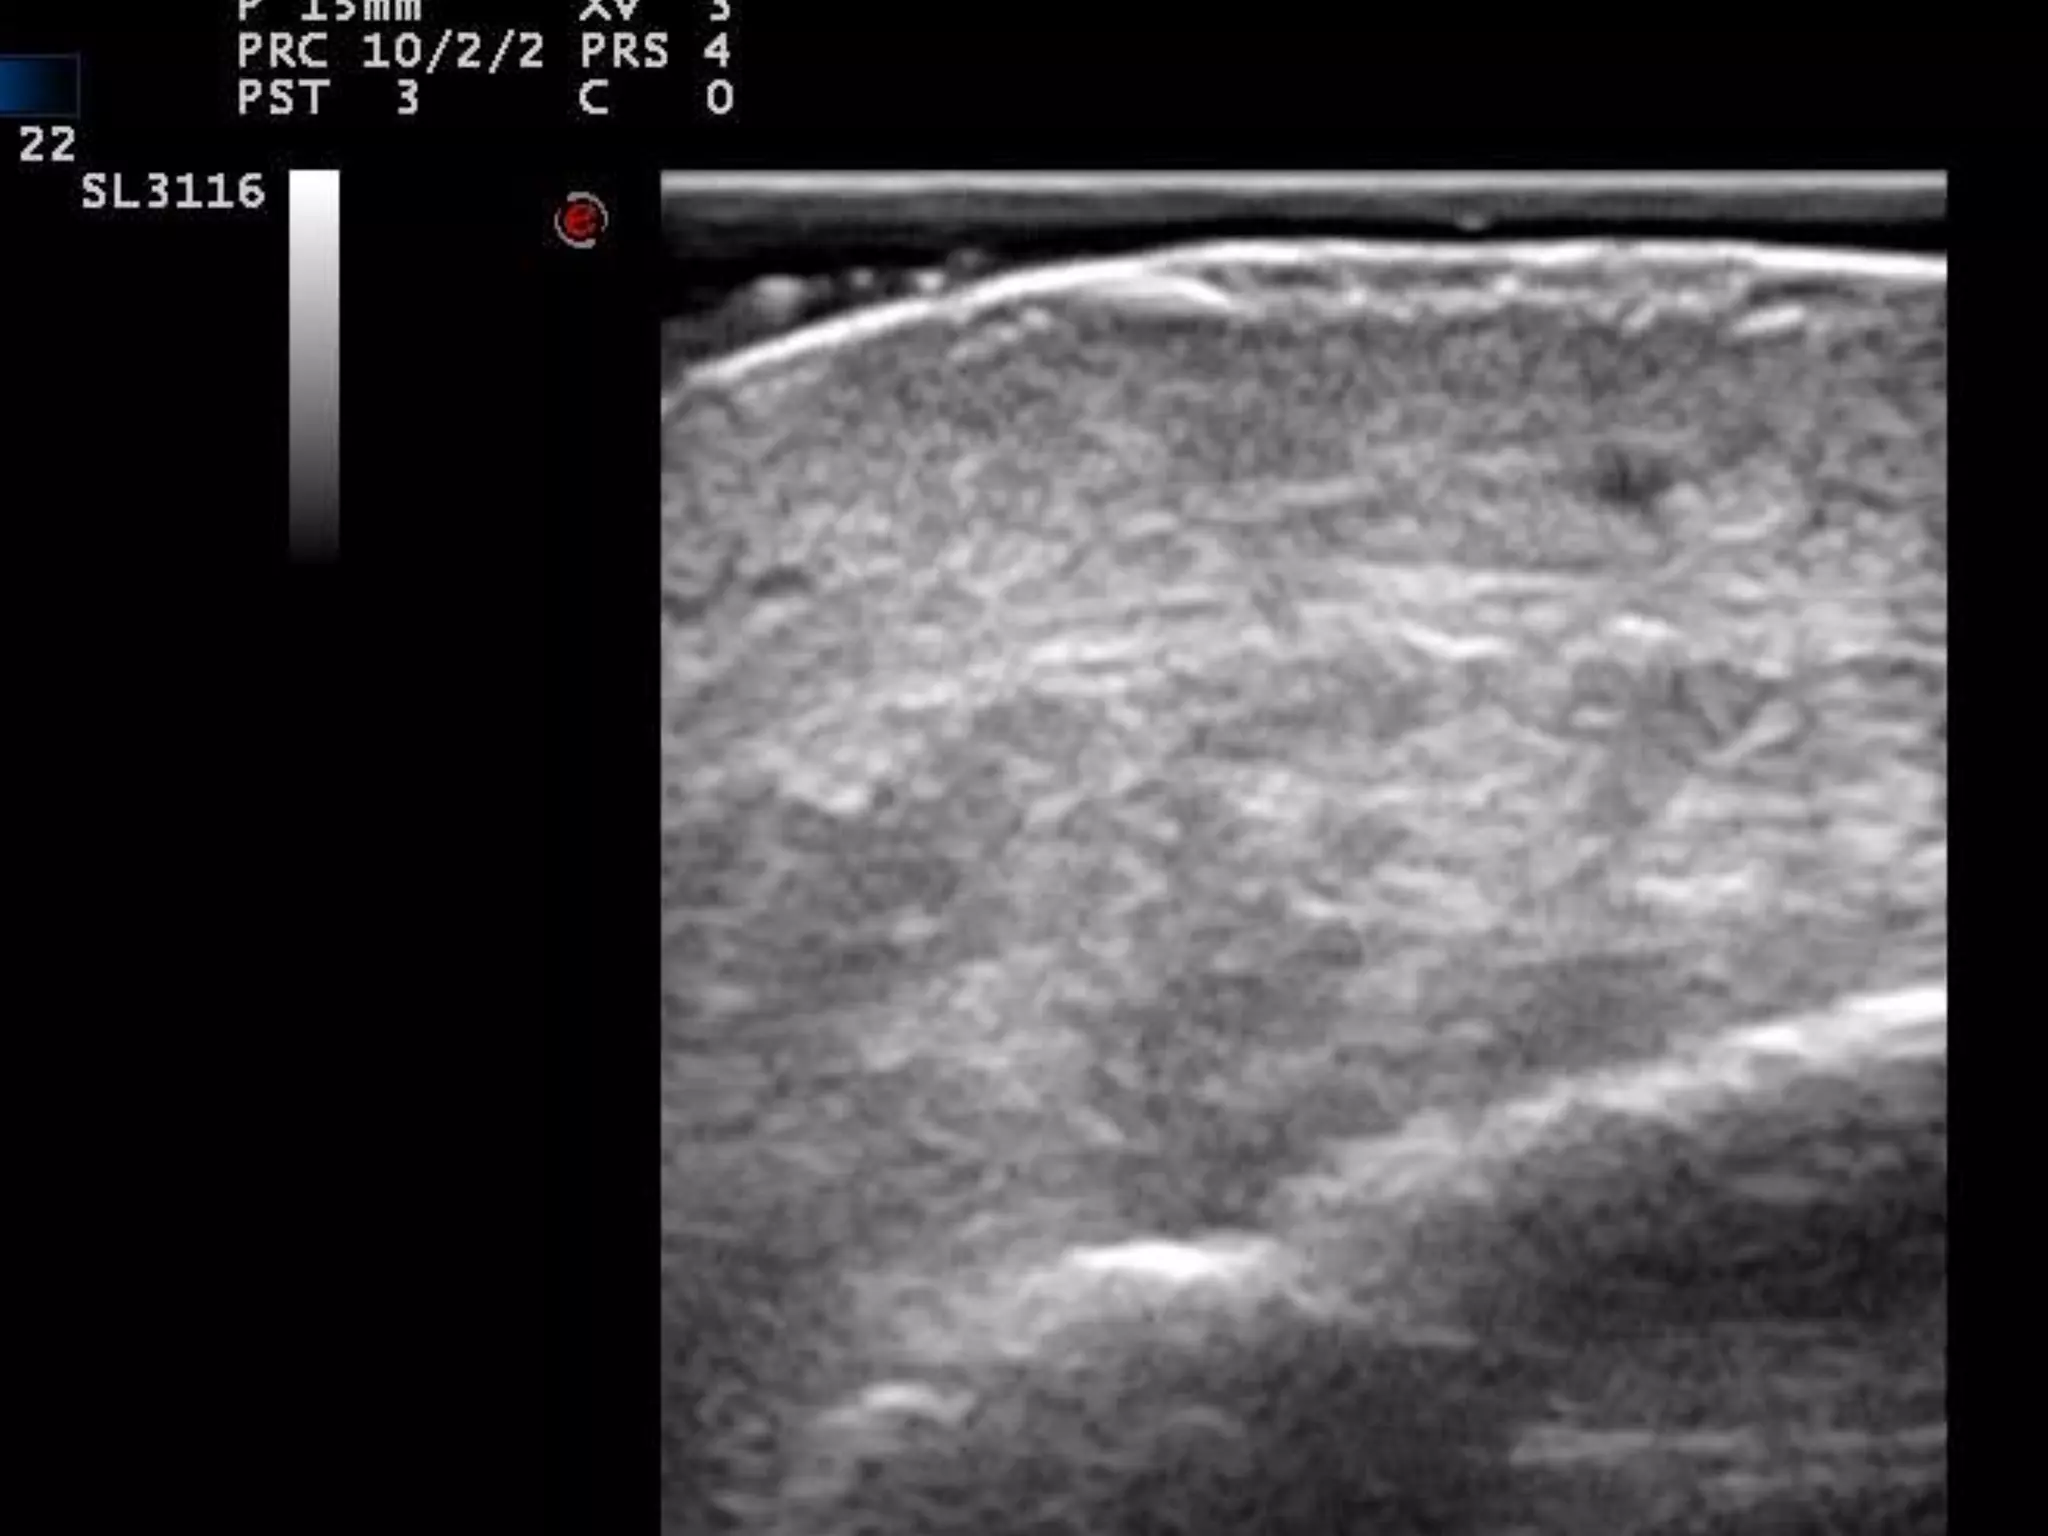

NORMAL

CUERO CABELLUDO

INFLAMADO

LOCALIZACION DE INFLAMACION

FOLICULAR

TINEA CAPITIS

REGLAS “FÁCILES”

PARA DETECTAR INFLAMACION

1)La estructura inflamada se suele hacer

Hipoecoica = edema+células

2)El flujo Doppler Suele estar aumentado=

Aumento de flujo sanguíneo

3) COMPARAR, COMPARAR, COMPARAR